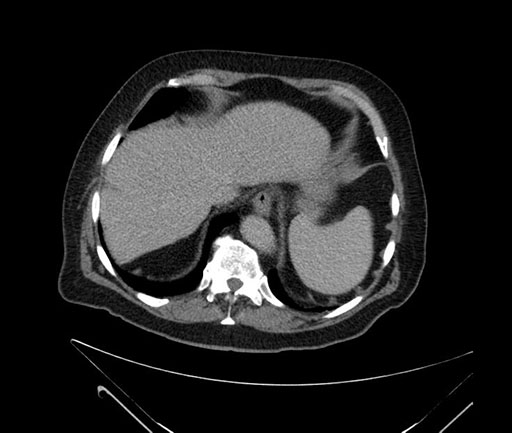

Axial - 3 months prior